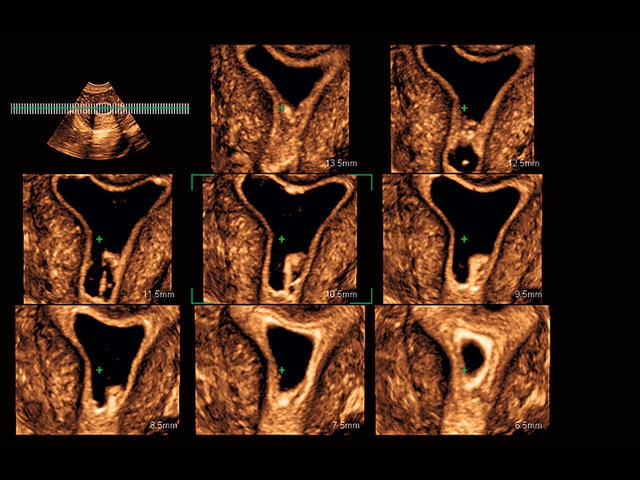

Обновленная версия легендарного УЗ-сканера. Стационарный аппарат экспертного класса Aplio 500 Toshiba NEW, визуализирует анатомические структуры в высоком разрешении. Модель позволяет выявить микрокальцификаты, новообразования, нарушения в работе сердца, сосудов и мышц. Присутствует функция виртуальной эндоскопии, 4D-сканирования, эластометрии тканей, УЗИ с контрастированием. За повышение качества изображения отвечают технологии ApliPure и Superb Microvascular Imaging. Первая задействует возможности пространственного и частотного кодирования, формирует цельный визуальный ряд с сохранением клинических маркеров. Вторая улучшает отображение микрососудистого русла, используя доплеровский эффект. Модель оснащена 21-дюймовым монитором, имеет 4 активных порта. Возможно подключение педиатрических, интраоперационных, лапароскопических и чреспищеводных датчиков.

- Fly Thru. Виртуальная эндосонография обеспечивает построение трехмерной модели полостей, протоков и сосудов в рельном времени, облегчает организацию инвазивных процедур и динамических исследований. Посредством Fly Thru можно установить шунты и стенты, проводить точные оперативные вмешательства.

- D-THI.Режим дифференцированной тканевой гармоники, повышающий качество визуализации глубоко расположенных тканей. Получаемое изображение отличается высокой четкостью, не содержит дефектов в виде «заснеженных» и размытых участков.